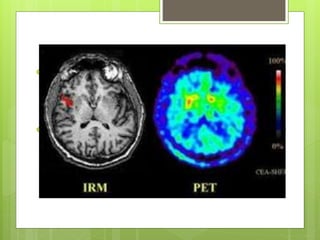

PET

 Técnica no invasiva de diagnóstico

del cuerpo humano.

 Detecta y analiza la distribución tridimensional que

adopta en el interior del cuerpo un de

vida media ultracorta

.

 Los tomógrafos detectan los emitidos

por el paciente  producto de una aniquilación entre

un positrón, emitido por el radiofármaco, y un electrón

cortical del cuerpo del paciente.

 Se que deben detectarse al mismo

tiempo en una ventana de tiempo adecuada (ns)

para formar una imagen.

PET  Técnica noinvasiva de diagnóstico del cuerpo humano.  Detecta y analiza la distribución tridimensional que adopta en el interior del cuerpo un de vida media ultracorta .

• 41.

 Los tomógrafosdetectan los emitidos por el paciente  producto de una aniquilación entre un positrón, emitido por el radiofármaco, y un electrón cortical del cuerpo del paciente.  Se que deben detectarse al mismo tiempo en una ventana de tiempo adecuada (ns) para formar una imagen.